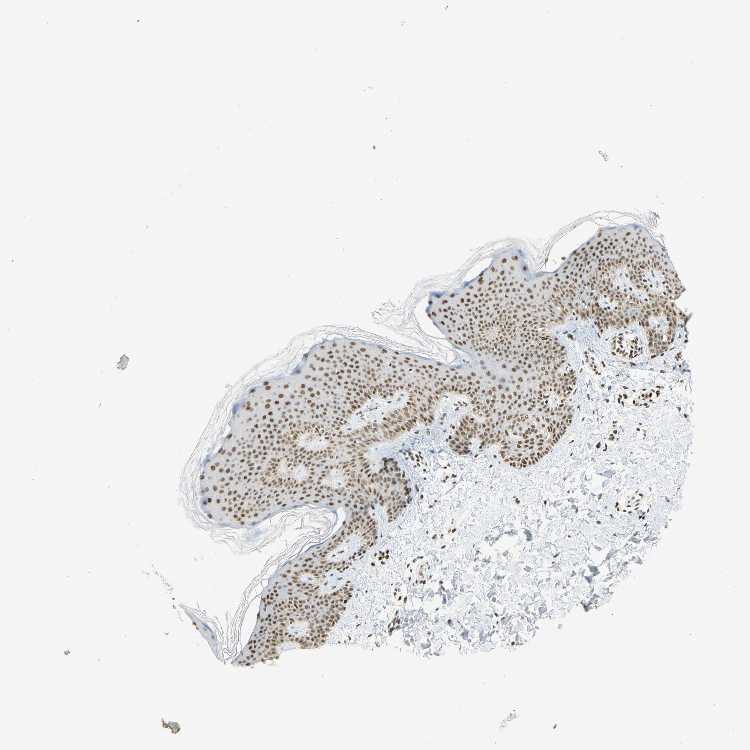

SKIN 1 - Antibody stainingi

Antibody staining in the annotated cell types in the current human tissue is reported as not detected, low, medium, or high, based on conventional immunohistochemistry profiling in selected tissues. This score is based on the combination of the staining intensity and fraction of stained cells.

Each image is clickable and will lead to virtual microscopy that enables deeper exploration of all samples and also displays staining intensity scores, fraction scores and subcellular localization as well as patient and tissue information for each sample.

Antibody HPA007290

Langerhans High

Fibroblasts High

Keratinocytes High

Melanocytes High

SKIN 2 - Antibody stainingi

Epidermal cells High